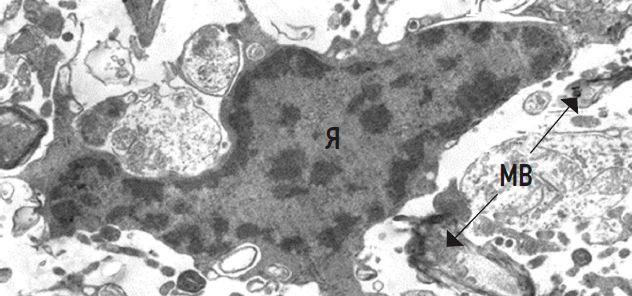

Further, in the control group, the chromatin distribution of some oligodendrocyte (OL) nuclei was consistent with apoptosis. The surrounding myelinated and unmyelinated fibers exhibited varying degrees of degeneration (Fig. 3). Such a morphology is indicative of the apoptosis-mediated functional inactivation of OLs.

Fig. 3. Oligodendrocyte rat spinal cord without treatment with signs of apoptosis. Я — nucleus with uneven and dense accumulations of heterochromatin in the karyoplasm; МВ — myelin fibers, ×10,000.

Рис. 3. Олигодендроцит спинного мозга крысы без лечения с признаками апоптоза: Я — ядро с неравномерными и плотными скоплениями гетерохроматина в кариоплазме; МВ — миелиновые волокна (стрелки), ×10 000.